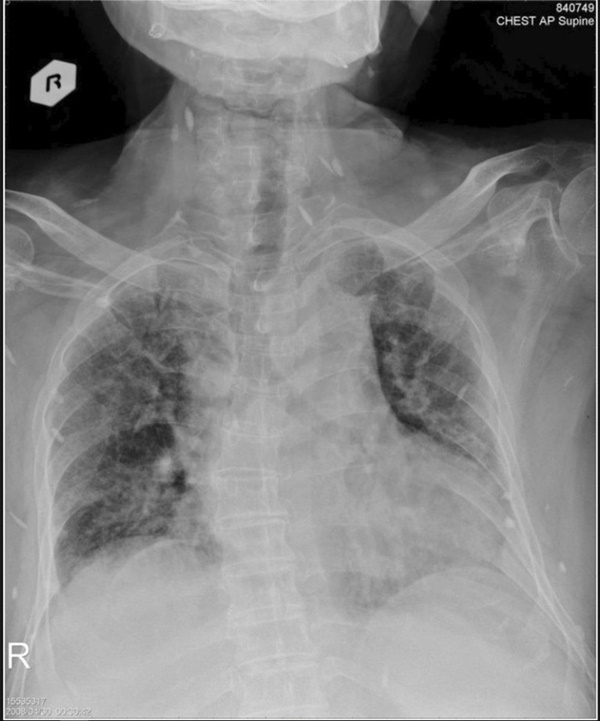

Qua hình ảnh chụp chiếu, dễ dàng nhận ra trứng sán dây xuất hiện trong não, cột sống, mông, cổ, ngực và chân cụ ông đã về hưu. Cụ được chẩn đoán mắc bệnh ấu trùng sán lợn. Đây là bệnh nhiễm trùng sán dây, thường là hậu quả của việc ăn thịt lợn bị nhiễm sán.

Hình ảnh chụp cho thấy các u nang ở cổ và ngực.

Tiến sĩ Ming-Pin Lin, một trong các tác giả viết về trường hợp của bệnh nhân 74 tuổi trên, cho biết, hình chụp chiếu thể hiện rõ "một bầu trời đầy sao" ấu trùng sán và còn tiết lộ cả tình trạng vôi hóa của cơ. Tiến sĩ chia sẻ thêm, biện pháp điều trị bao gồm thuốc kháng ký sinh trùng, steroids và đặt thiết bị vào não để giảm áp lực lên não gây ra bởi hiện tượng ứ dịch.